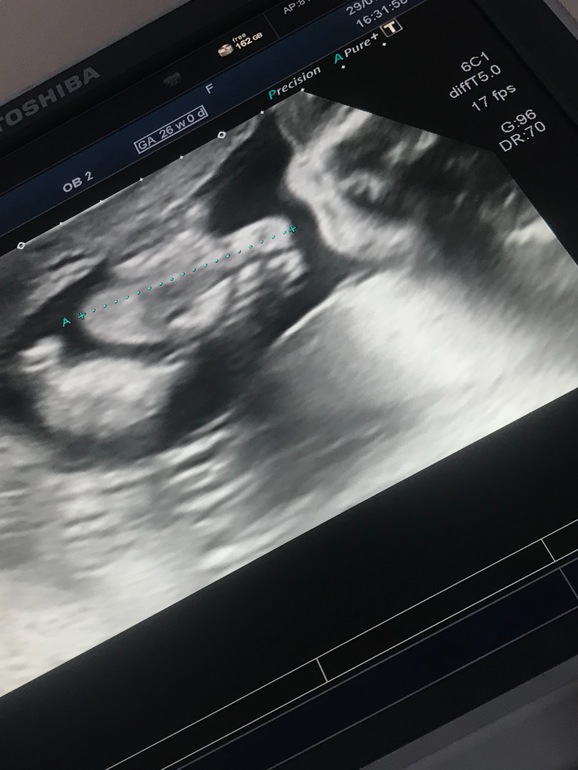

25+5, немного фото малыша с УЗИ

УЗИ, КТГ, доплерВрач решила, что раз уж я живу в 10 минутах от ЖК (хотя это уже давно не так, и я езжу из МО 🙈, но никому об этом не говорю чтобы не менять консультацию) - можно назначить доплер за 2 часа до его проведения 😅

Узи делала та же врач, которая нашла впервые сердцебиение нашего кренделька ☺️ Очень отзывчивая приятная женщина. Сначала посмотрела собственно кровотоки и все, что нужно по допплерометрии, а потом устроила развлекательную программу, показывая части тела крохи)

Сынок лежит попой вниз, весит 948 грамм 💪🏼